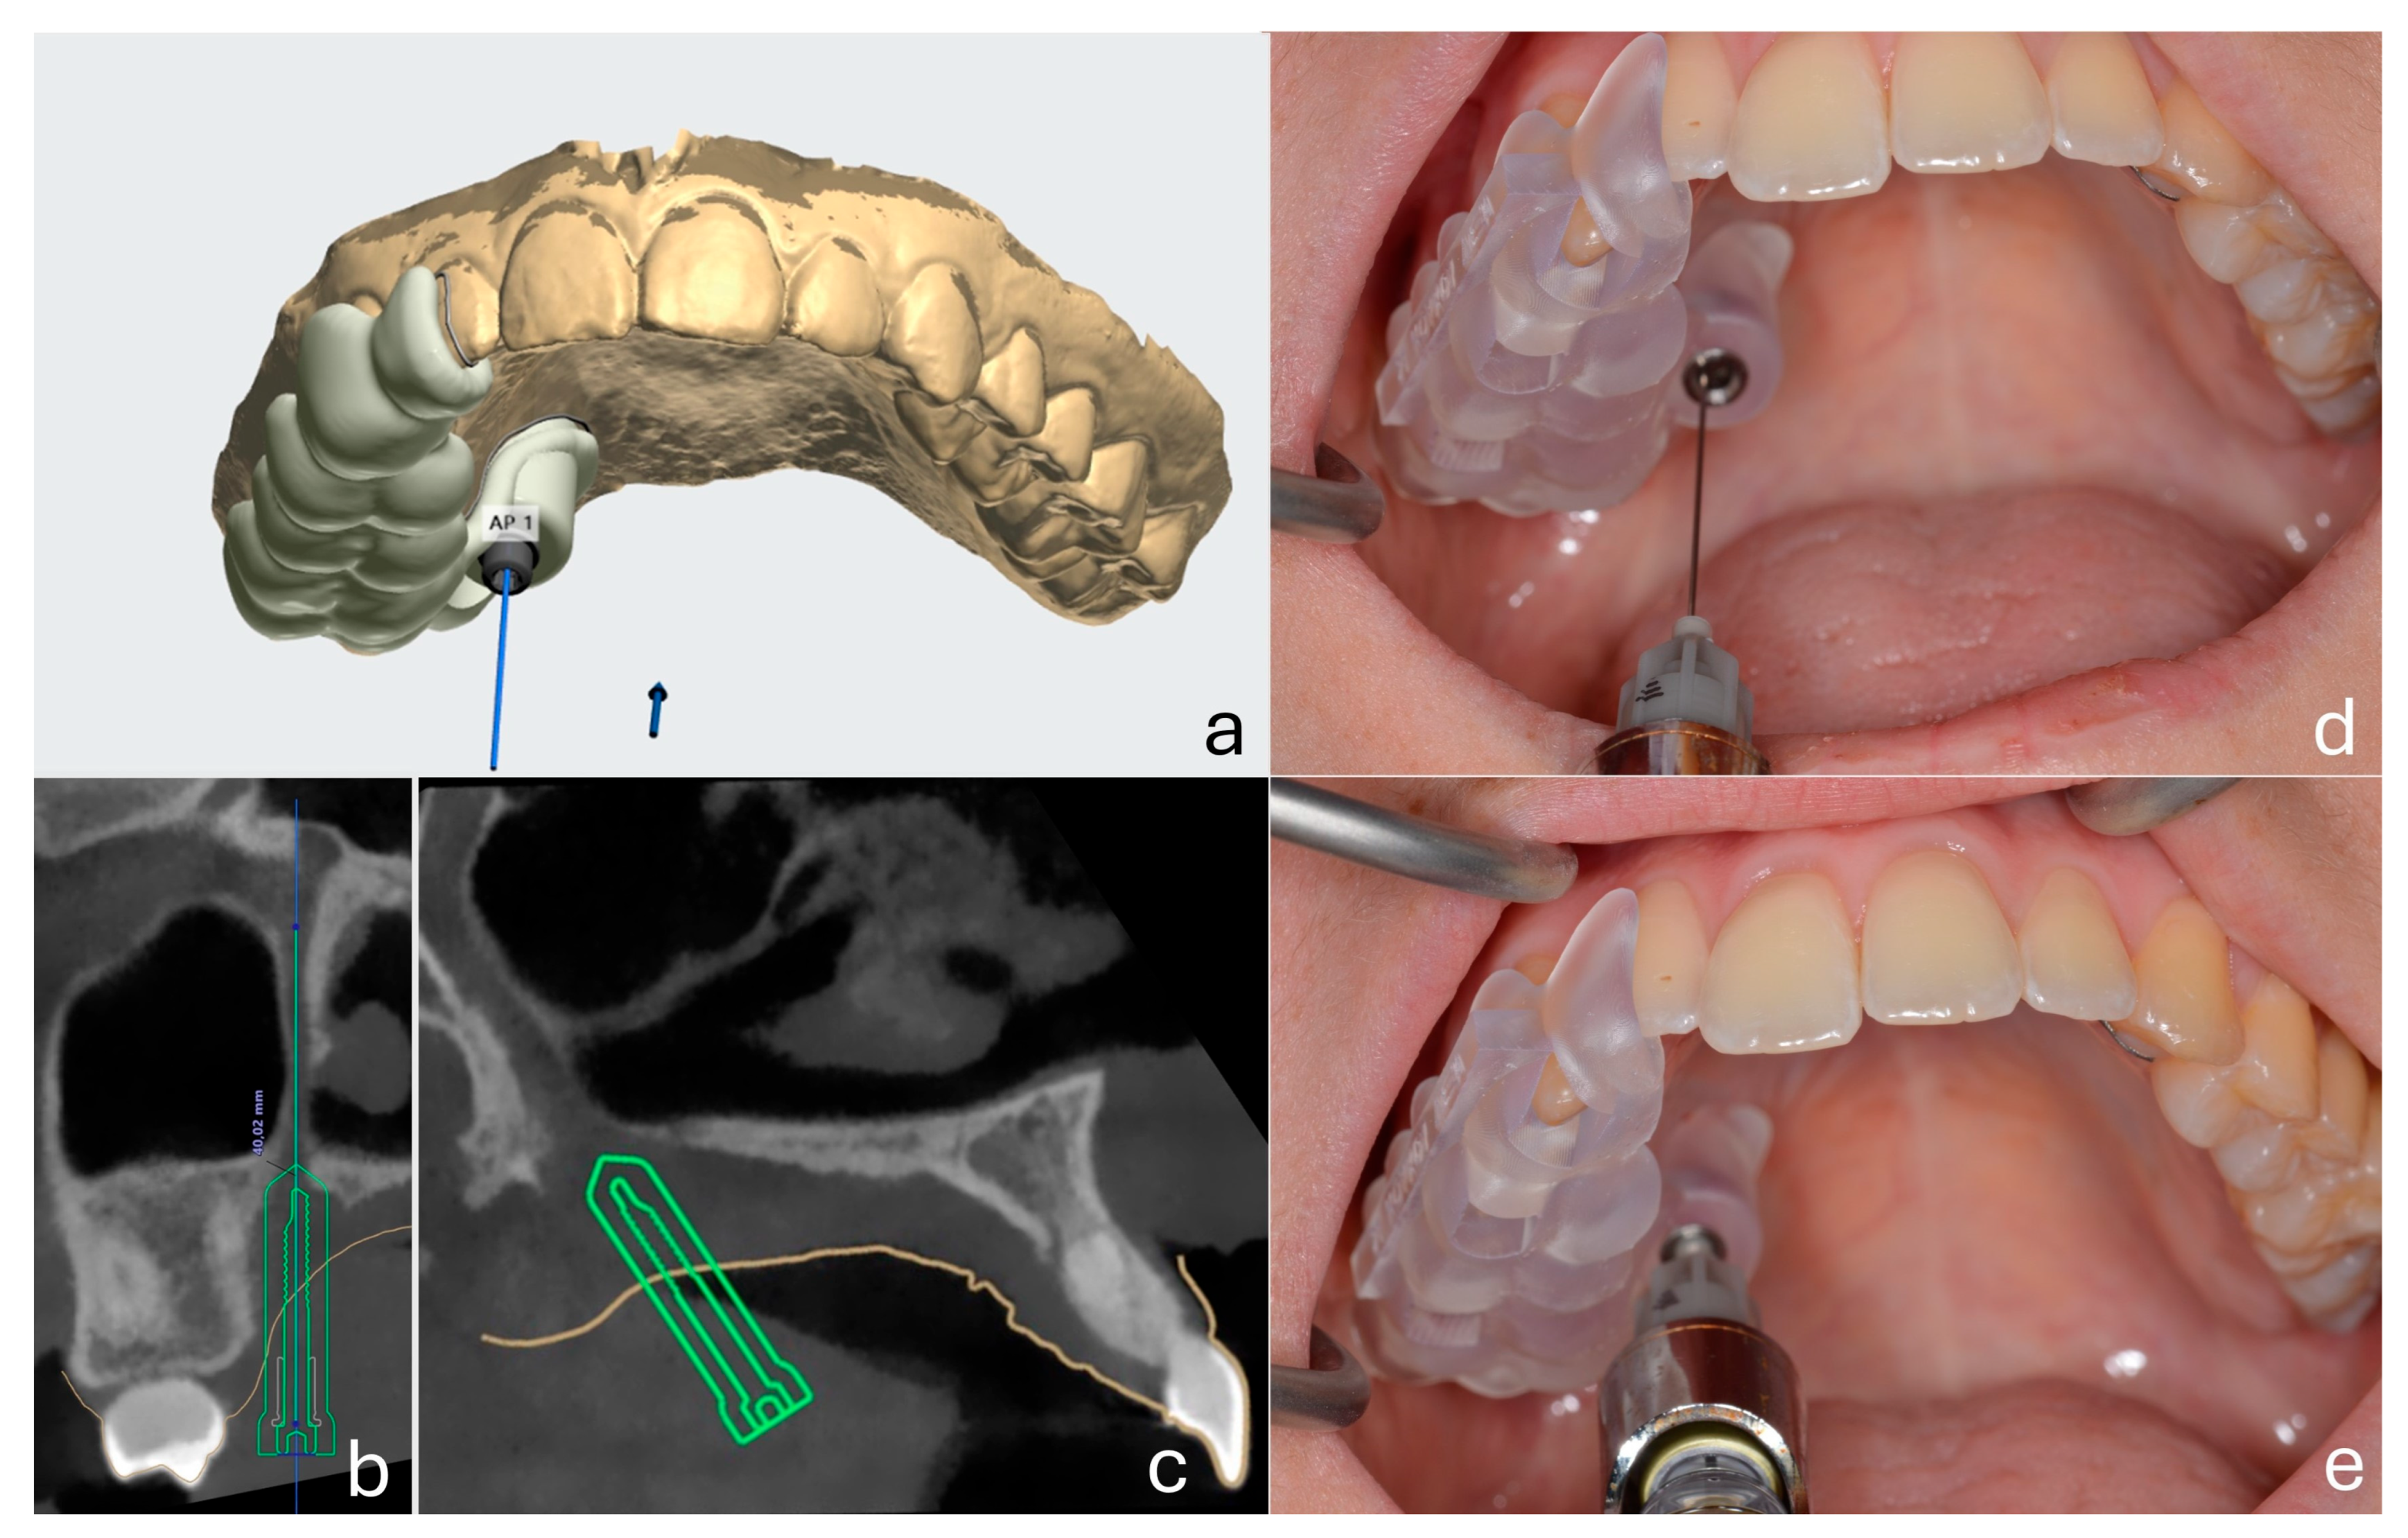

2.6. Maxillary Nerve Anesthesia Protocol

After baseline testing, the customized surgical guide was positioned intraorally. A 27G long dental needle (Septoject®, Septodont, Saint-Maur-des-Fossés, France) was inserted through the guide and advanced into the greater palatine canal under controlled depth and angulation to perform the maxillary nerve block. The metallic sleeve of the guide functioned as both an angulation stabilizer and a depth limiter. The hub of the needle contacted the sleeve ring, providing a physical stop and ensuring standardized penetration depth across all patients. The anesthetic solution administered was 2% lidocaine with 1:80.000 epinephrine (Lignospan Special®, Septodont, Saint-Maur-des-Fossés, France), with a total volume of 1.8 mL delivered per patient. All nerve block procedures and measurements were performed by the same experienced oral surgeon to ensure consistency and minimize operator-related variability. The technique for performing the nerve block was based on the method described by Malamed [27] (Figure 1).

Figure 1. Computer-guided maxillary nerve block via the greater palatine canal using a customized surgical guide. (a) Virtual planning of the guide and insertion trajectory on maxillary digital cast. (b,c) CBCT sections showing the planned path of needle insertion into the pterygopalatine canal in relation to surrounding anatomy. (d,e) Clinical application of the 3D-printed guide with the needle inserted through the metallic sleeve during local anesthetic administration.